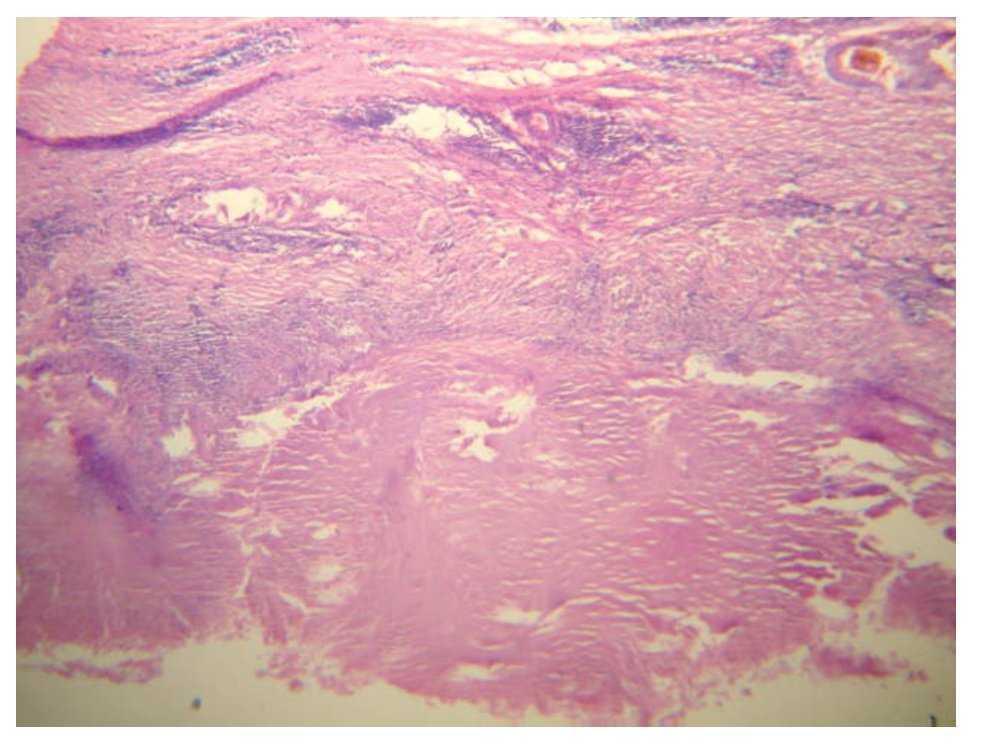

En la urografía excretora se apreció aumento de la silueta renal izquierda en la placa simple; con la aplicación de medio de contraste, se apreció exclusión renal izquierda; el riñón contralateral sin alteraciones (Figura 1).

Imagen 1. Urografía excretora. Con la aplicación de medio de contraste, se aprecia exclusión renal izquierda; el riñón contra-lateral sin alteraciones (placas tomadas a los cinco [izq] y 90 [der] minutos